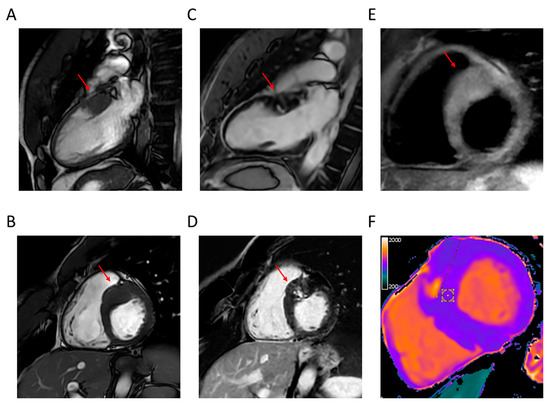

4.1. LV Hypertrophy

4.2. Apical Aneurysm

4.3. LVOTO

4.4. LV Function